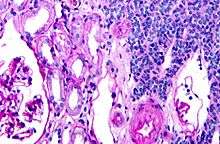

| Micrograph of a metanephric adenoma with structures reminiscent of those seen in papillary renal cell carcinoma. H&E stain. | |

Metanephric adenoma (MA)is a rare, benign tumour of the kidney, that can have a microscopic appearance similar to a nephroblastoma (Wilms tumours),[1] or a papillary renal cell carcinoma.

Metanephric adenoma is diagnosed histologically. The tumours can be located at upper pole, lower pole and mid-hilar region of the kidney; they are well circumscribed but unencapsulated, tan pink, with possible cystic and hemorrhagic foci. They show a uniform architecture of closely packed acinar or tubular structures of mature and bland appearance with scanty interposed stroma.[3][4][5][6][7] Cells are small with dark staining nuclei and inconspicuous nucleoli. Blastema is absent whereas calcospherites may be present. Glomeruloid figures are a striking finding, reminiscent of early fetal metenephric tissue. The lumen of the acini may contain otherwise epithelial infoldings or fibrillary material but it is quite often empty. Mitoses are conspicuously absent.[3][4][5][6][7] In the series reported by Jones et al. tumour cells were reactive for Leu7 in 3 cases of 5, to vimentine in 4 of 6, to cytocheratin in 2 of 6, to epithelial membrane antigen in 1 of 6 cases and muscle specific antigen in 1 of 6.[8] Olgac et al. found that intense and diffuse immunoreactivity for alpha-methylacyl-CoA racemase (AMACR) is useful in differentiating renal cell carcinoma from MA but a panel including AMACR, CK7 and CD57 is better in this differential diagnosis.[9] Differential diagnosis may be quite difficult indeed as exemplified by the three malignancies initially diagnosed as MA that later metastasized, in the report by Pins et al.[10]